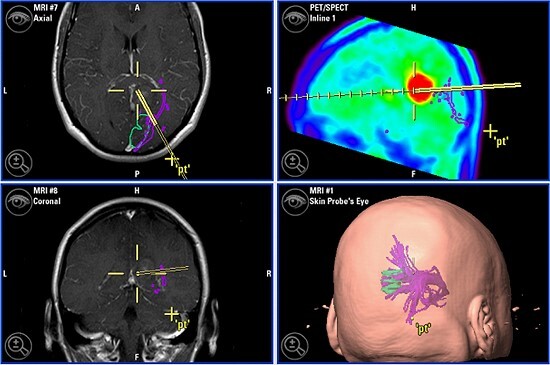

Mithilfe von MRT-Bildern und einem speziellen Computerprogramm bereiten die Neurochirurgen des Westküstenklinikums Operationen am Gehirn vor. (Grafik: WKK)